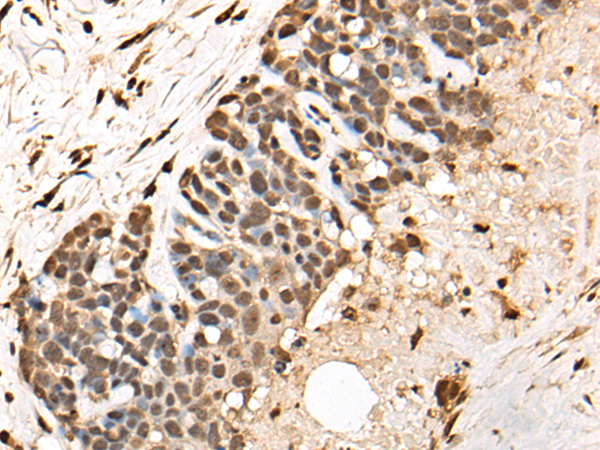

IHC positive control: |

Human thyroid cancer and human cervical cancer |

IHC Recommend dilution: |

25-100 |